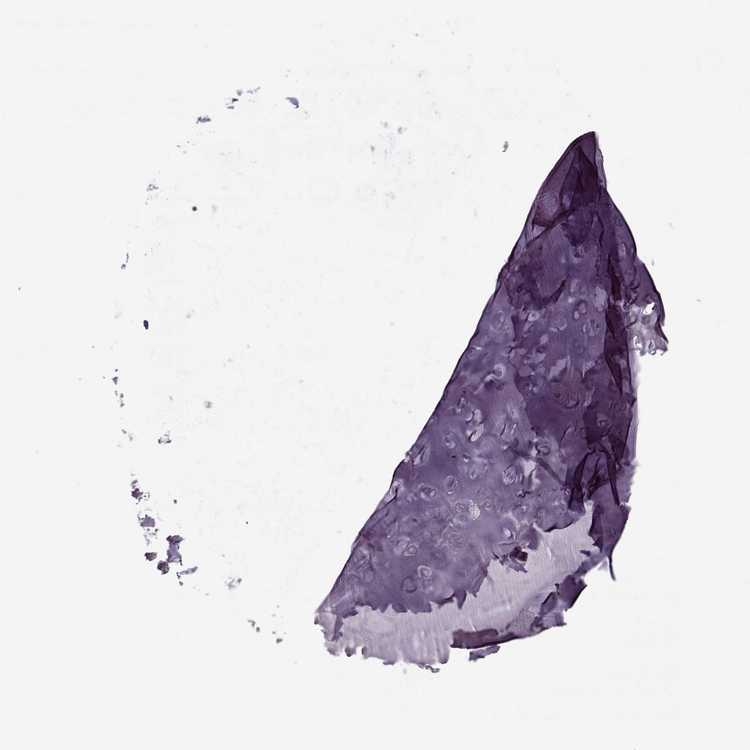

SOFT TISSUE 1 - Antibody stainingi

Antibody staining in the annotated cell types in the current human tissue is reported as not detected, low, medium, or high, based on conventional immunohistochemistry profiling in selected tissues. This score is based on the combination of the staining intensity and fraction of stained cells.

Each image is clickable and will lead to virtual microscopy that enables deeper exploration of all samples and also displays staining intensity scores, fraction scores and subcellular localization as well as patient and tissue information for each sample.

Antibody HPA071133

Chondrocytes Not detected

Fibroblasts Not detected

Peripheral nerve Not detected